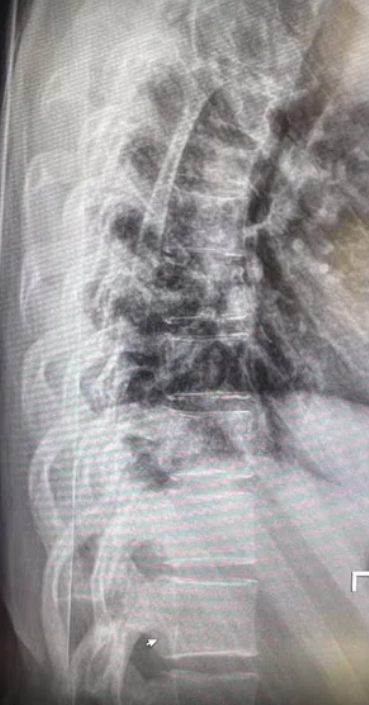

最近,一名新加坡女网红爆料,她在从英国飞新加坡的航班上遭遇严重乱流,导致脊椎骨折,从此对飞行产生阴影,飞机一开始晃动,她就会异常的惊恐、焦虑。

而一名叫Mia的新加坡女网红在网上爆料到,当时她正好在洗手间。飞机剧烈颠簸时,她狠狠摔倒了,最终导致脊椎骨折